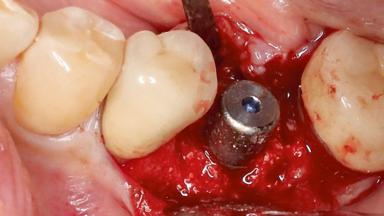

Despite anti-infective surgical treatment, some patients may experience recurrent infection and progressive bone loss requiring additional treatment. Removal of Implant Due to Recurrent Infection describes a conservative approach using an implant retrieval tool without the need for excessive bone removal or use of a trephine.

A 70-year-old female patient was referred by her general dentist to the periodontist for assessment and management of an infection associated with implant 36. The general dentist had noted suppuration on probing during examination.